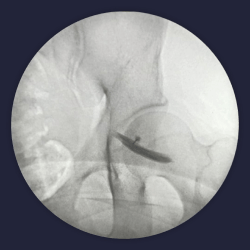

Intra op fluoroscopy images of piriformis injection